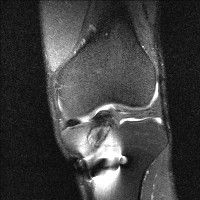

무릎 mri 간단히 봐주실 수 있으시나요 ㅠㅠ

안녕하세요 8년전 십자인대 수술하고 최근 무리한 운동에 무릎 불편감이 생겨서

mri 찍었습니다.

진단결과는 첫 찍은 병원에서 활액막염 이라는 진단을 받았습니다. 혹시 봐주실 수 있으실까요?

올라온 MRI가 단편적이라서 정확한 진단에 어려움이 있지만 십자인대에는 큰 이상이 있지는 않은것 같으며, 무릎관절내 물이 있는 것으로 보아 활액막염의 진단이 맞을 것 같습니다.

하지만 단편적인 영상이기 때문에 촬영병원에서 정확한 판독지 등을 받으시는 것이 좋겠습니다.